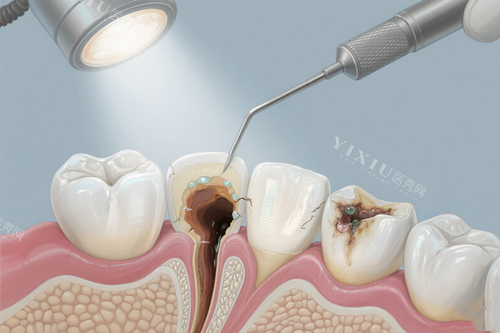

天津中牙口腔位于天津市南开区中南道南侧中南广场东区一号楼3层,交通便利,周边配套设施完善。作为一家口腔专科医院,中牙口腔拥有正规医疗执业资质,诊疗范围涵盖口腔全科项目,包括牙体牙髓病、牙周病、口腔粘膜病、儿童口腔、口腔颌面外科、口腔修复、口腔正畸、口腔种植及预防口腔等多个可靠领域。

显微根管治疗系统:大幅提高根管治疗的正确度和成功几率,尤其对复杂根管、钙化根管的处理更具优势。

激光治疗仪:应用于牙周治疗、软组织修整等,减少出血和肿胀,加速术后修复。